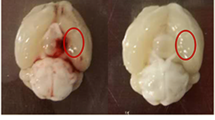

To induce SAH in mice, we used intravascular filament perforation that resulted exclusively in extraparenchymal bleeding. While the procedure of SAH induction in mice was highly standardized, the consequences including the clinical course were less predictable. Therefore, at the end of experiments all animals were thoroughly assessed; mice presenting with intracerebral hemorrhage were thus excluded from further studies. This type of evaluation consisted of a macroscopical analysis of bleeding into the subarachnoid space at the brain base at different time points (Fig. 2a) and a microscopic assessment of hematoxylin/eosin (HE)-stained brain sections at early time points (Fig. 2b). An iron stain proved the occurrence of SAH while excluding intraparenchymal bleeding, also at later stages (Fig. 2b, right).

Murine experiments. a Illustrative macroscopic findings in perfused brains. After sham operation, no subarachnoid blood could be detected around the brain (left). Early after induction of experimental SAH (day 2), a diffuse bleeding was detected in the subarachnoid compartment (middle), where it remained after washout by intra-arterial perfusion. CSF-circulation subsequently washed out blood in the subarachnoid space. No residual blood could be detected macroscopically at day 28 (right). b To prove the occurrence of subarachnoid hemorrhage, hematoxylin/eosin stainings were performed at day 2 after the bleeding (left, arrow pointing at SAH). To rule out parenchymal damage by ischemia or intraparenchymal bleeding, hematoxylin/eosin staining was performed at day 28 (middle, arrow pointing at site of former hemorrhage). To prove the occurrence of the hemorrhage at the end of the experiments, when no residual blood could be seen macroscopically, iron staining for detection of hemoglobin was done (right), showing hem residuals in the ambient cistern (arrows). Scalebars 500 µm. c Staining for Iba-1-positive cells in the brain parenchyma after experimental SAH showed the initiation of an early accumulation near the site of the induction of the hemorrhage (left). The highest accumulation of Iba-1-positive cells was seen on day 14 after the hemorrhage, surpassing basal ganglia, reaching the corpus callosum and even cortical brain areas (middle). At the end of the observation period, a less dense but global accumulation of Iba-1-positive cells was seen throughout both hemispheres (right). d Stainings for extracellular APP revealed an accumulation around the site of cellular accumulation near the brain base on day 4 (left). This accumulation culminated around day 14, showing massive extracellular APP accumulation, that paralleled the cellular reaction (middle). Towards day 28, less extracellular APP could be stained (right). Scalebars (lower magnification) = 500 µm, scalebars (higher magnification) = 100 µm, n = 6 per time point. e Quantification of Iba-1-positive cells per HPF (left), and evaluation of the total covered area of the respective brain sections by Iba-1-positive cells (middle) and extracellular APP (right). ANOVA: **p < 0.01, ***p < 0.001, ****p < 0.0001